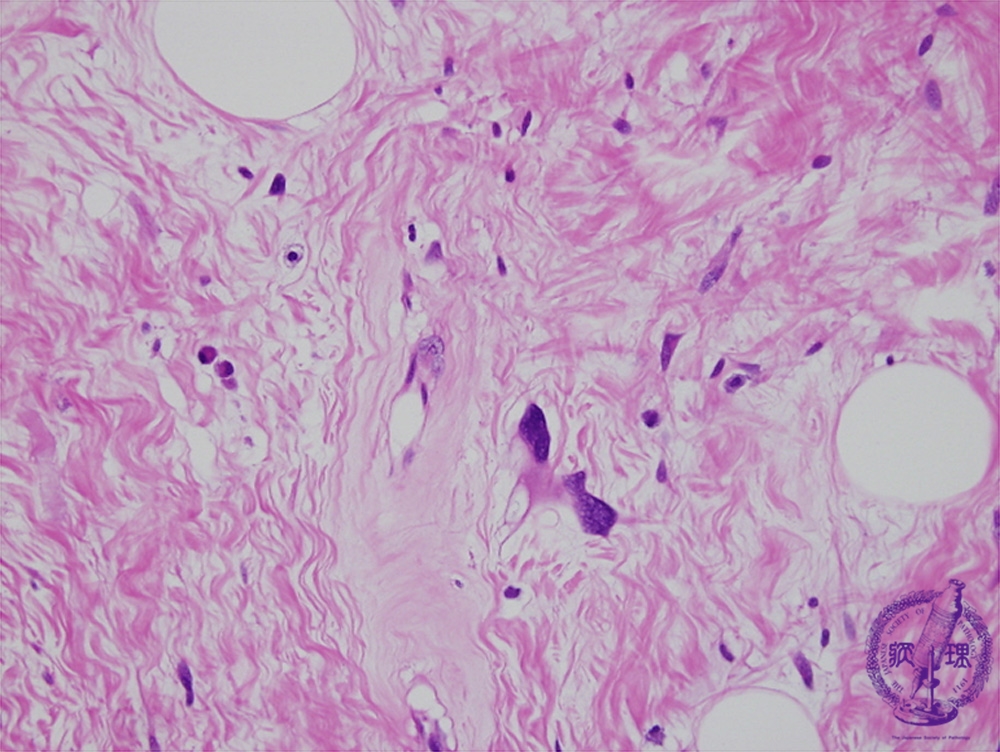

Microscopic findings (H.E. high power view): Hyperchromatic tumor cells with atypical nuclei scattered in the collagenous tissue.